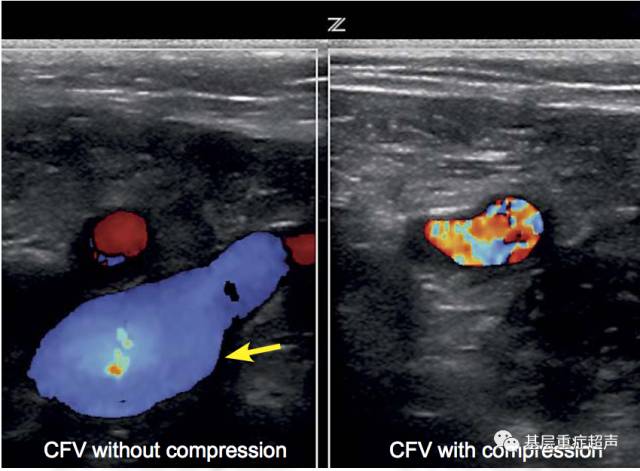

股总静脉检查

DVT在短轴的超声成像,无受压的静脉